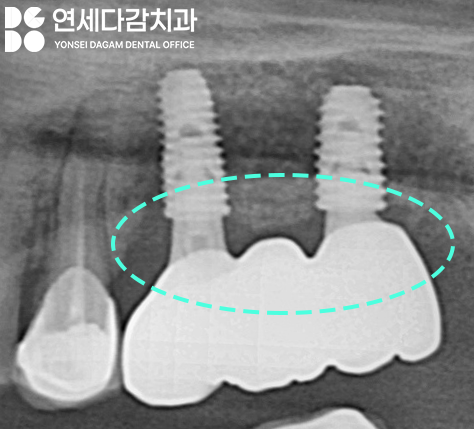

문정역 치과 에서 보여드린

엑스레이를 살펴보면,

임플란트와 크라운이 연결된

부품의 형태가 다른 것을 볼 수 있습니다.

이 부위를 지대주 (=어버트먼트, abutment) 라고 하는데,

엑스레이 상에서 표시한 부위를

살펴보면 보철물이 살짝 뜬 것처럼

보이는 것을 볼 수 있죠.

이런 미세한 부적합은

육안으로 확인되지 않을 수 있어도

잇몸 밑으로 이런 형태를

가지고 있기 때문에

장기적으로 봤을 때

문제를 일으킬 가능성이 높습니다.